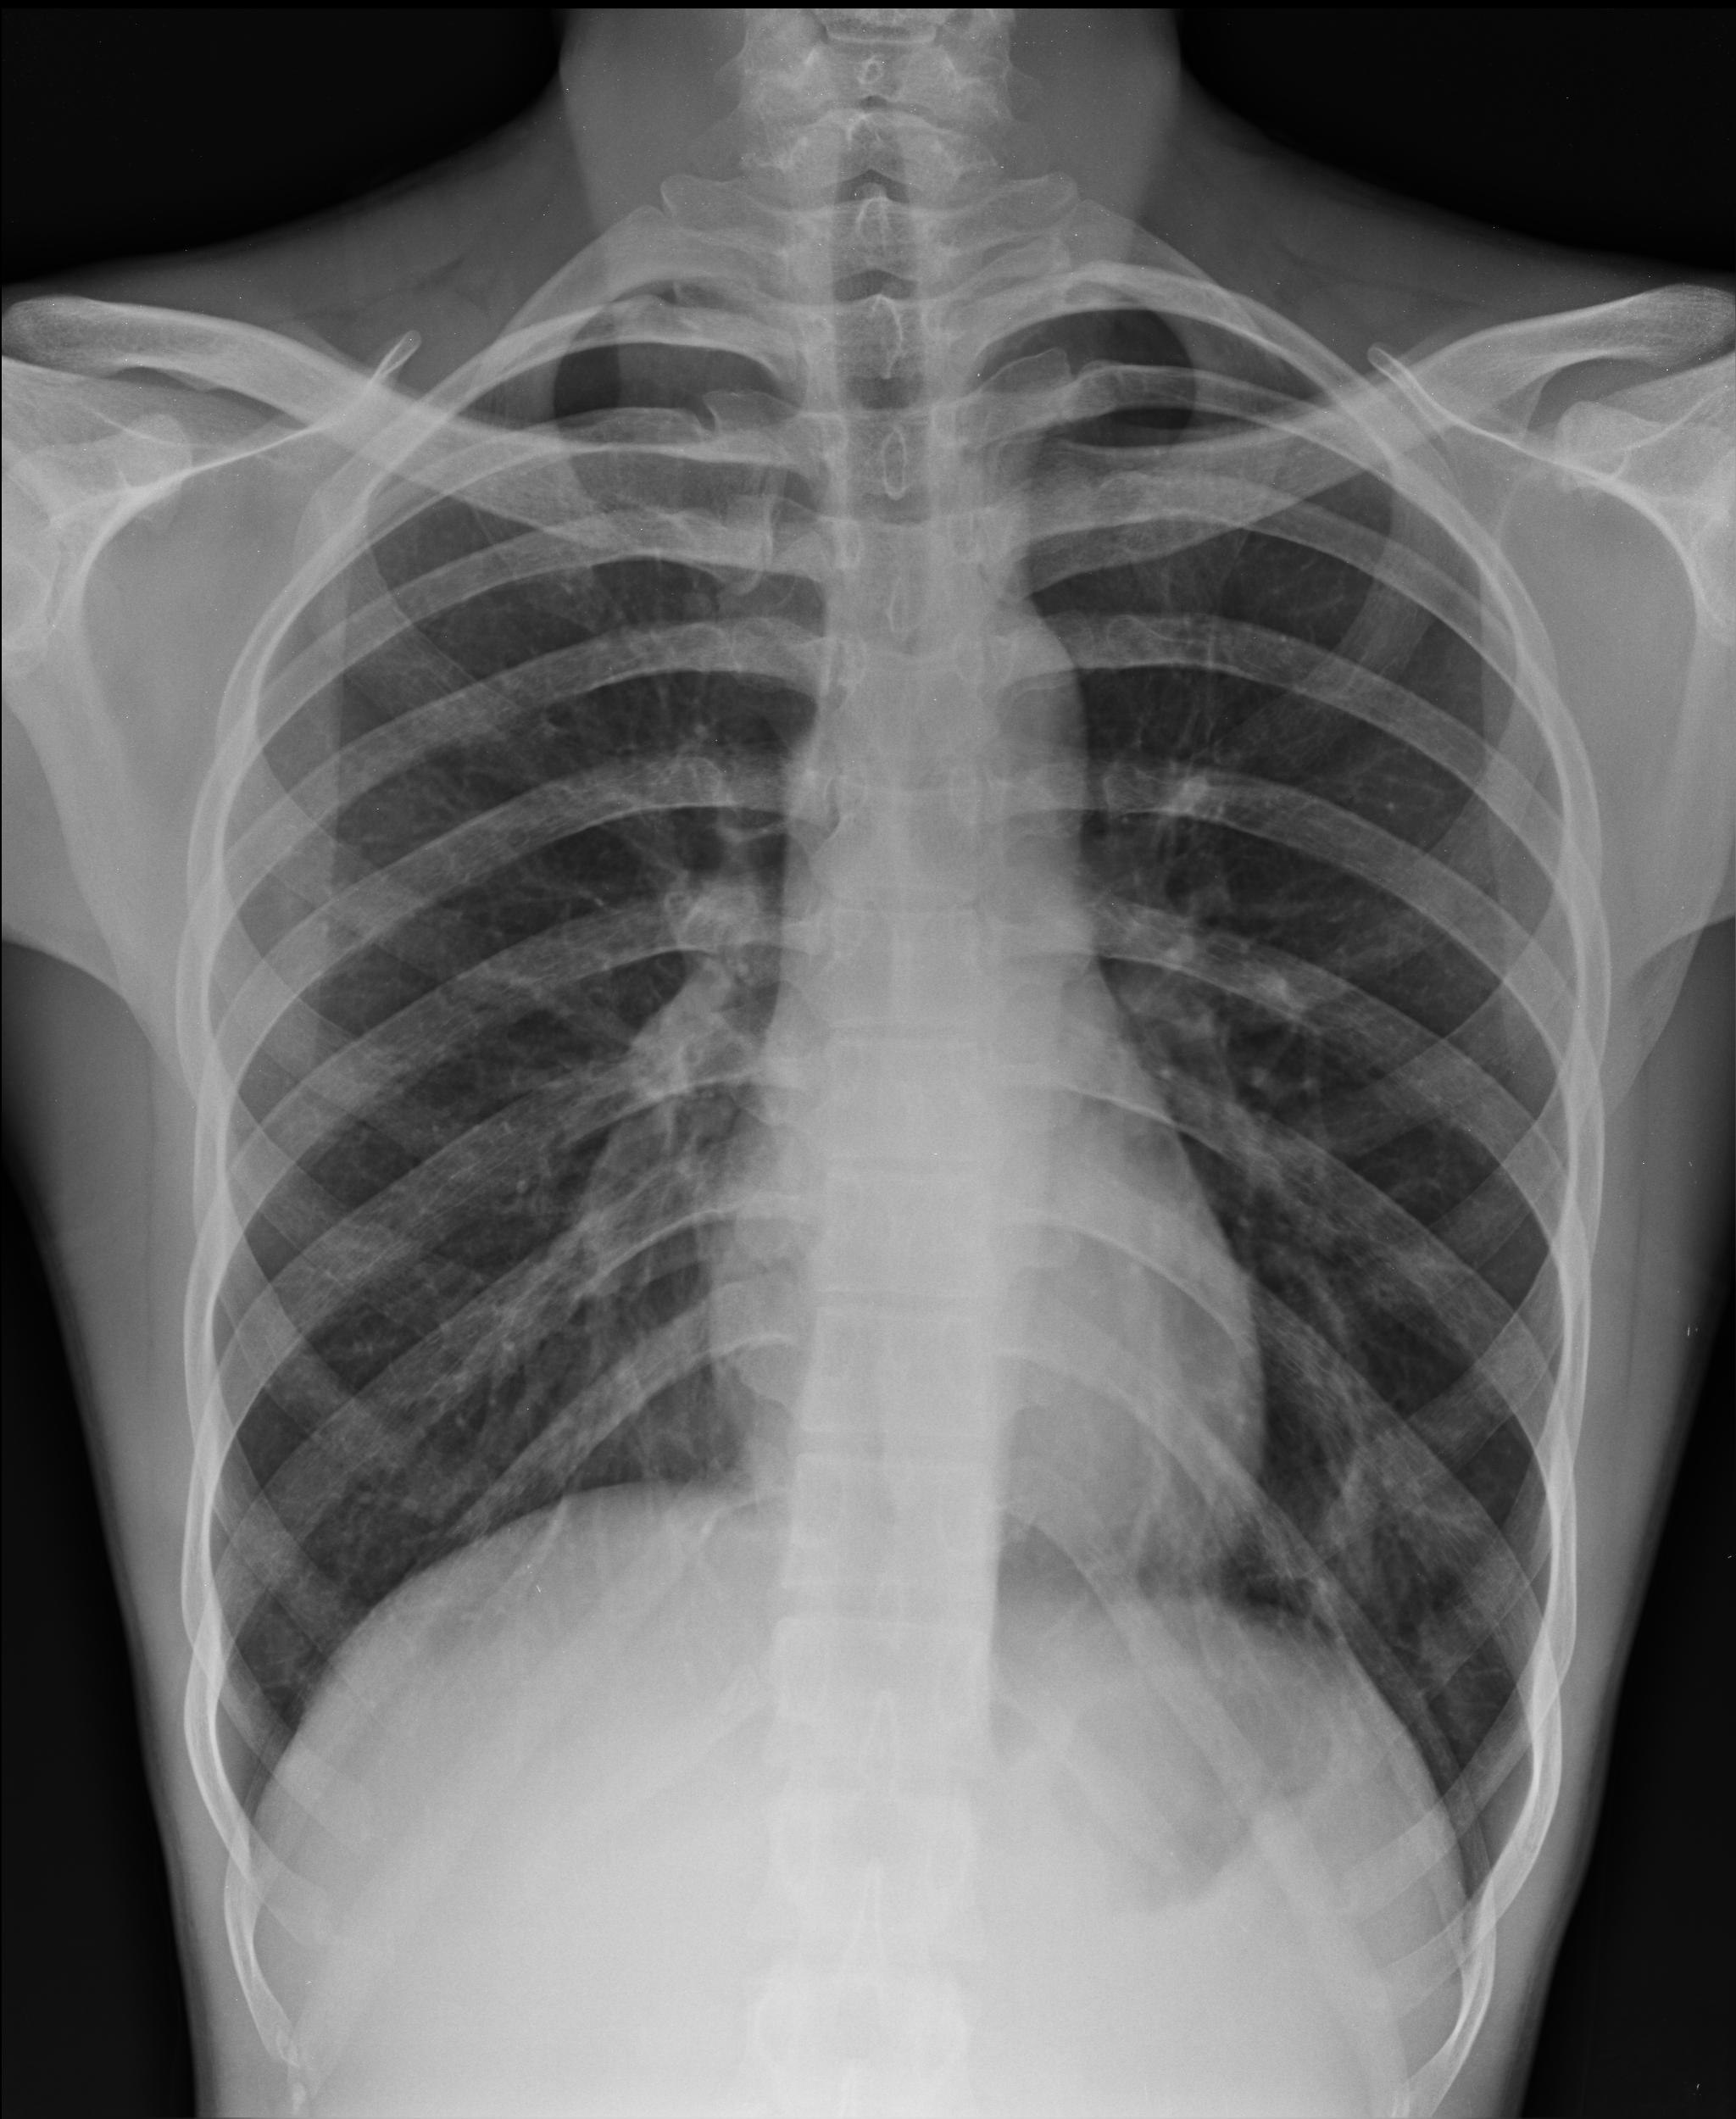

Figure 1:

PA chest x-ray.